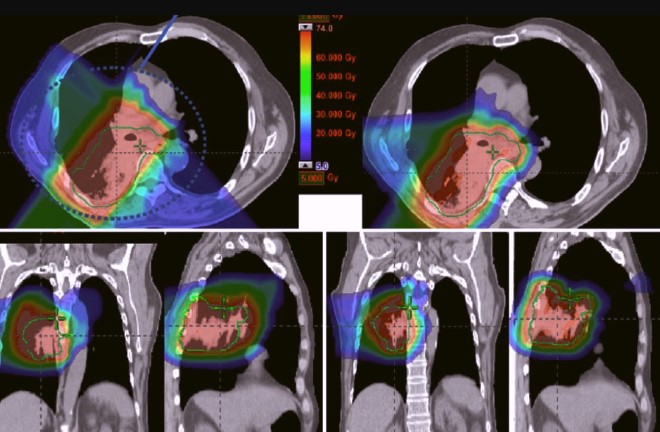

2. Лучевая терапия.

Этот метод применяется при комбинированном лечении. Современные способы ее проведения позволяют обеспечить максимально возможный доступ лекарства к пораженной зоне, за счет чего снижается негативное воздействие на другие внутренние органы.